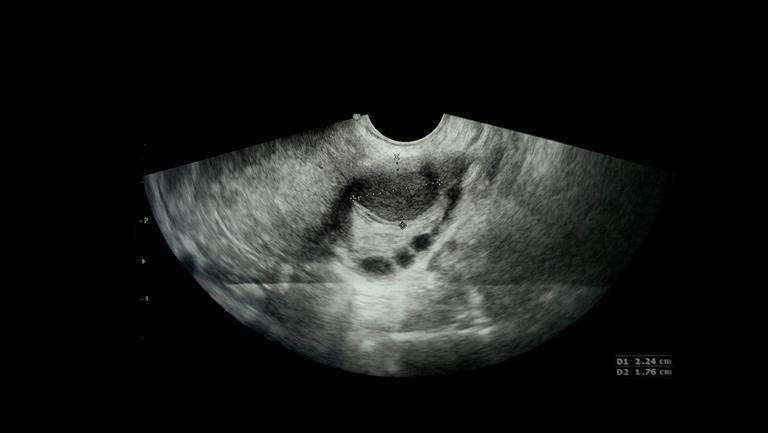

Testarea HLA este cea mai importanta metoda prin care afli daca esti compatibil genetic cu celulele stem ale copilului tau. Costul unei testari HLA complete poate ajunge pana la 1.500 Euro.

Testarea si identificarea compatibilitatii profilului genetic al parintelui/fratelui cu proba de celule stem, stocata in cadrul bancii daneze a Stem SURE, scade in mod considerabil riscul aparitiei GVHD (graft versus host disease), boala de reject al grefei versus gazda, cunoscuta popular ca reactia de respingere a transplantului, ce poate duce de la complicatii majore pana la decesul persoanei care a primit transplantul, aceasta argumentand inca o data importanta acestei testari.